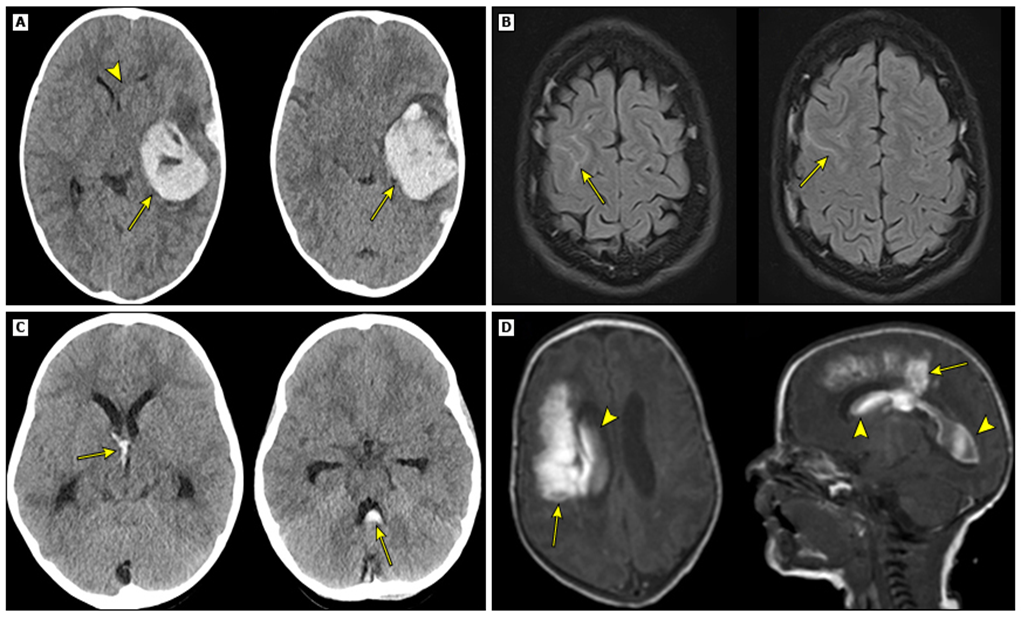

–თავის ტრავმა ან ქალასშიდა სისხლდენა – შემთხვევათა უმრავლესობაში, კომპიუტერული ტომოგრაფია წარმოადგენს თავის ტრავმის ან ქალასშიდა სისხლჩაქცევის სავარაუდო საწყისი შეფასებისთვის სასურველ ვიზუალიზაციის მეთოდს (სურათი 3).

სურათი 3.

ჰემორაგიული ინსულტის ქვეტიპები.

(A) აქსიალური თავის კომპიუტერული ტომოგრაფია, რომელიც აჩვენებს მარცხენა საფეთქლის მწვავე ინსულტის დიდ კერას (ისრები) მიმდებარე შეშუპებით და მასის ზემოქმედებით მარცხენა ლატერალურ პარკუჭზე (ისრის თავი) შუა ხაზის მარცხნიდან მარჯვნივ გადახრით. ამ პაციენტში სისხლდენის გამომწვევი მიზეზი იყო VIII ფაქტორის დეფიციტი.

(B) აქსიალური T2/FLAIR MRI თანმიმდევრობა, რომელიც აჩვენებს არატრავმულ SAH-ს, რომელიც ჩანს როგორც ჰიპერინტენსიური სიგნალი მარჯვენა შუბლის წილის ტვინის ამოზნექილ ნაწილში (ისრები).

(C) აქსიალური თავის კომპიუტერული ტომოგრაფია იზოლირებული IVH-ით მესამე (C, მარცხენა პანელი) და მეოთხე (C, მარჯვენა პანელი) პარკუჭებში (ისრები), რომლებიც დაკავშირებულია ჰიდროცეფალიასთან.

(D) აქსიალური (D, მარცხენა პანელი) და საგიტალური (D, მარჯვენა პანელი) T1-სიმძლავრის MRI თანმიმდევრობა, რომელიც აჩვენებს მარჯვენა ფრონტო-პარიეტალურ ინსულტის დიდ კერას (ისრები) ინტრავენტრიკულური გაფართოებით მთელ მარჯვენა ლატერალურ პარკუჭში (ისრის თავები).

CT: კომპიუტერული ტომოგრაფია; IPH: ინტრაპარენქიმული სისხლდენა; FLAIR: სითხით შესუსტებული ინვერსიული აღდგენა; MRI მაგნიტურ-რეზონანსული ტომოგრაფია: SAH სუბარაქნოიდული ჰემორაგია.